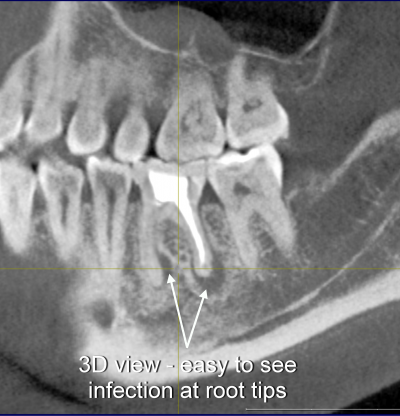

Liz was aware that there was an infection in her jaw. Despite her local dentist not being overly concerned with what they saw, we knew that this infection was putting her body at high risk for systemic infection. Liz flew to Portland and, after her BDC New Patient Experience, had her lower left first molar removed following our protocol. As you can see below, the 3-D x-ray is far superior in showing the infection that her root canal-treated tooth caused in her jaw bone.